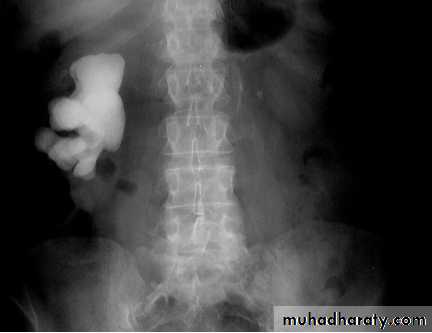

KUB

The IVU series consist of:1-KUB film…To identify any calcification like stones or nephrocalcinosis.

CALCULIMost renal stones are calcified and show varying density on plain x-ray films.

Pure uric acid & xanthine stones are radiolucent on plain radiography, but are well seen at CT or US.

Plain film is more sensitive than US for detecting ureteric calculi.